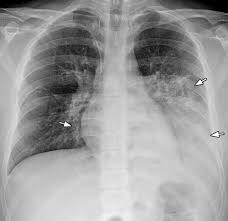

Radiographic Approach To The Coughing Pet Mspca Angell from www.mspca.org Small cell lung cancer (sclc). The condition of your lungs. How do dogs get pneumonia? However, many primary lung tumors are identified. This growth can spread beyond the lung by the process of metastasis into nearby tissue or other parts of the body. } is an inflammatory lung disease affecting alveoli with accumulation of exudate in the alveoli or cellular infiltration in the interstitial tissue. A tumor site located in the lung tissue or subpleural: Pneumonia is a lung infection, and it has shown links to the development and progression of lung cancer.

Some people also may develop pain in the chest wall. Metastatic lung cancers (cancers that spread to the lungs from other locations) are much more common in dogs than primary lung cancers. This growth can spread beyond the lung by the process of metastasis into nearby tissue or other parts of the body. This achieved even a higher precision than before. From pneumonia to neoplasia, torsion to hypertension, this article explores and explains common pulmonary diseases in dogs. Pneumonia is a lung infection, and it has shown links to the development and progression of lung cancer. A nationwide analysis in china. How do dogs get pneumonia? Documents similar to pneumonia xray. Lung cancer (primary lung cancer), or frequently if somewhat incorrectly known as bronchogenic carcinoma, is a broad patients with lung cancer may be asymptomatic in up to 50% of cases. Most cancers that start in the lung, known as primary. Failure, pneumonia, allergic lung disease, and lung. A new challenge for prevention and therapy.

Lung cancer is the top cause of cancer deaths in both men and women. Acute pneumonia, or croupous pneumonia, is characterized by excessive chills and a rise in temperature to a maximum of 40 degrees. Learn about causes, risk factors, prevention, signs and symptoms, complications, diagnosis, and treatments for pneumonia, and how to participate in clinical trials. Some people also may develop pain in the chest wall. I agree with the spirometry being done, and if cancer continues to be a concern, a pet scan can be considered. Who is most at risk of each? Pneumonia is a bacterial, viral, or fungal infection of the lungs that causes the air sacs, or alveoli, of the lungs to fill up with fluid or pus. Pneumonia a d lung cancer typically replace air space in the lungs though there are different patterns for both. A nationwide analysis in china. Lung cancer, also known as lung carcinoma, is a malignant lung tumor characterized by uncontrolled cell growth in tissues of the lung. A new challenge for prevention and therapy. This achieved even a higher precision than before. Metastatic lung cancers (cancers that spread to the lungs from other locations) are much more common in dogs than primary lung cancers.

Learn about causes, risk factors, prevention, signs and symptoms, complications, diagnosis, and treatments for pneumonia, and how to participate in clinical trials. Who is most at risk of each? Metastatic lung cancers (cancers that spread to the lungs from other locations) are much more common in dogs than primary lung cancers. What are the overlapping symptoms and outlook? Chronic bronchitis is a disease in dogs affecting the smaller airways that branch out from the trachea (windpipe). Simptom clippings rigler (place of entry of the bronchus). A tumor site located in the lung tissue or subpleural: Pneumonia a d lung cancer typically replace air space in the lungs though there are different patterns for both. A new challenge for prevention and therapy. Lung cancer, also known as lung carcinoma, is a malignant lung tumor characterized by uncontrolled cell growth in tissues of the lung. Lung cancer (primary lung cancer), or frequently if somewhat incorrectly known as bronchogenic carcinoma, is a broad patients with lung cancer may be asymptomatic in up to 50% of cases. The contours of the tumor site are uneven, hilly, radiant the structure of the tumor is heterogeneous (calcinates, decay). Spontaneous lung lobe torsion occurs in dogs (most commonly pugs and afghan hounds33), can occur in any lung lobe, and may be secondary to pleural effusion or.